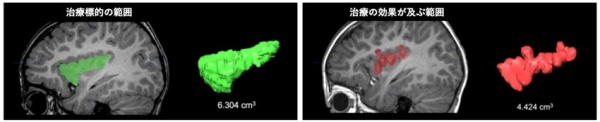

5mm凝固病変の周囲にT1強調画像で低信号となる領域が存在し、この範囲が最終的に治療の効果が及ぶ領域であることがわかりました。これらの領域の体積を比較することで、計画時の治療標的のうち70~78%の範囲を治療できることがわかりました(図4)。

図4:治療標的のうち70~78%の範囲が治療されていることが 明らかになった。